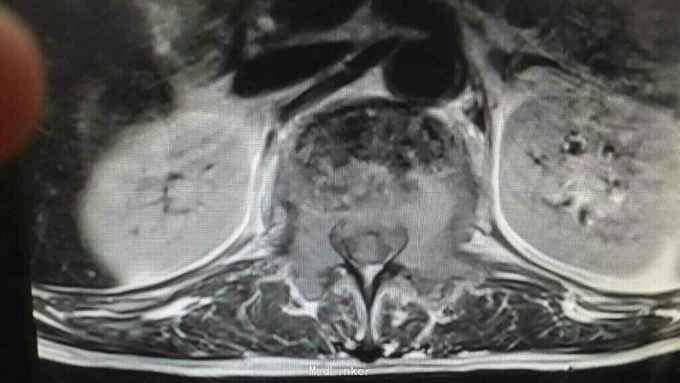

查体:脊柱生理曲度存在,无明显前凸,侧弯或后凸畸形,约胸10至腰5节段压痛及叩击痛阳性,双下肢肌张力正常,双侧股四头肌肌力约三级,双侧足背伸肌,踇背伸肌肌力约四级,双侧“4”字试验阴性,双侧直腿抬高试验阴性。肛周约15cm范围皮肤感觉减退。 辅助检查:肿瘤标志物无明显异常,血沉达120mm/h,血红蛋白111g/l,球蛋白与白蛋白比值倒置,血免疫球蛋白IgG达46.2g/l,明显升高。血清Kappa轻链与血清Lambda轻链比值明显升高。余辅助检查见下图。

通过影像学,实验室检查,骨髓穿刺检查及行CT引导下穿刺病理结果,患者多发性骨髓瘤诊断已明确。于全麻下行“腰1椎体病理性骨折病变清除减压内固定术”,术中可见病变压迫脊髓明显,彻底减压,术中出血较多,椎体破坏较重,未予骨水泥塑型,术后患者症状缓解明显,拆线后转至血液科进一步治疗。

多发性骨髓瘤是一种单克隆的浆细胞异常增生所致的恶性肿瘤,常以骨骼症状为首发,以脊柱最常累及,本例患者主要手术指征为持续且无法缓解的骨痛,并存在脊髓和神经根压迫症状,,主要影像学表现为穿凿样溶骨性改变,周围无硬化改变。很多全身骨现象无明显的阳性表现,增加了诊断的难度,上面提到的血沉升高,贫血,球白比倒置,血免疫球蛋白升高,骨髓穿刺综合判断,诊断明确后,一般行姑息性手术治疗,一般预后较差,随访见到生存期最长为4年。